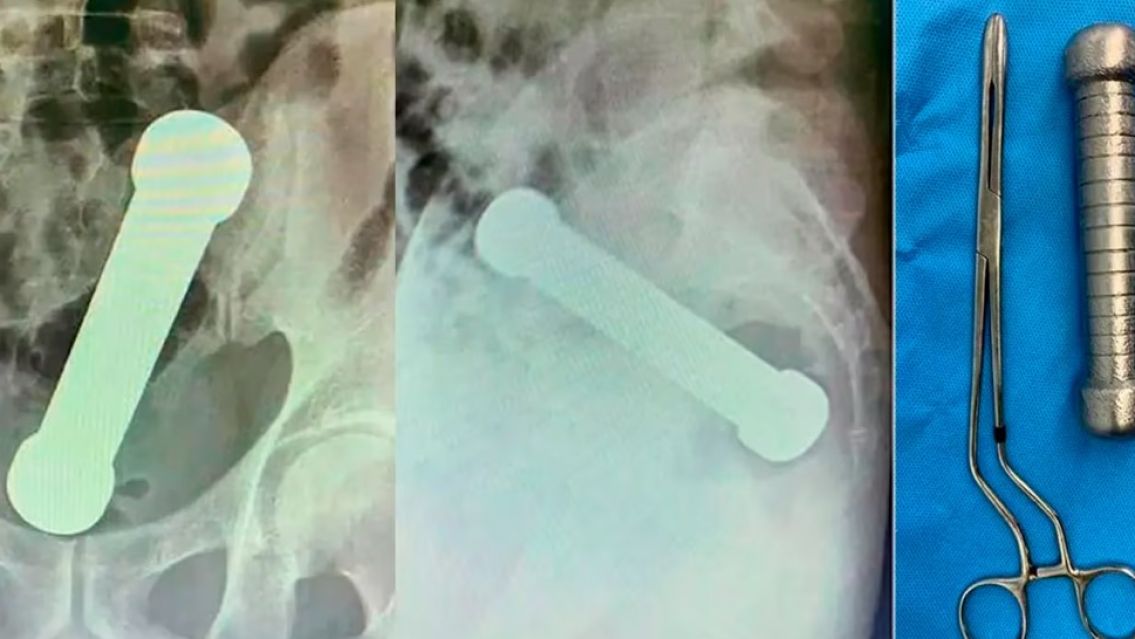

En abril de 2022, un ciudadano brasileño de 54 años se vio involucrado en un incidente insólito que recientemente volvió a viralizarse por las impactantes imágenes de las radiografías. El hombre fue hospitalizado de urgencia en Manaos, noroeste de Brasil, después de presentar dolor abdominal, náuseas y dificultad para defecar.

Las radiografías revelaron la presencia de un objeto metálico de 4.4 libras y casi 20 cm en su ano, lo que llevó a los médicos a realizar una operación de emergencia para extraerle una mancuerna. Según los informes médicos, esta situación fue resultado de un peligroso juego sexual.

En un intento inicial de extracción mediante pinzas, los cirujanos optaron finalmente por intervenir quirúrgicamente para evitar posibles complicaciones, como la perforación anal u otras lesiones graves. La operación fue exitosa, y el paciente fue dado de alta tres días después sin complicaciones.